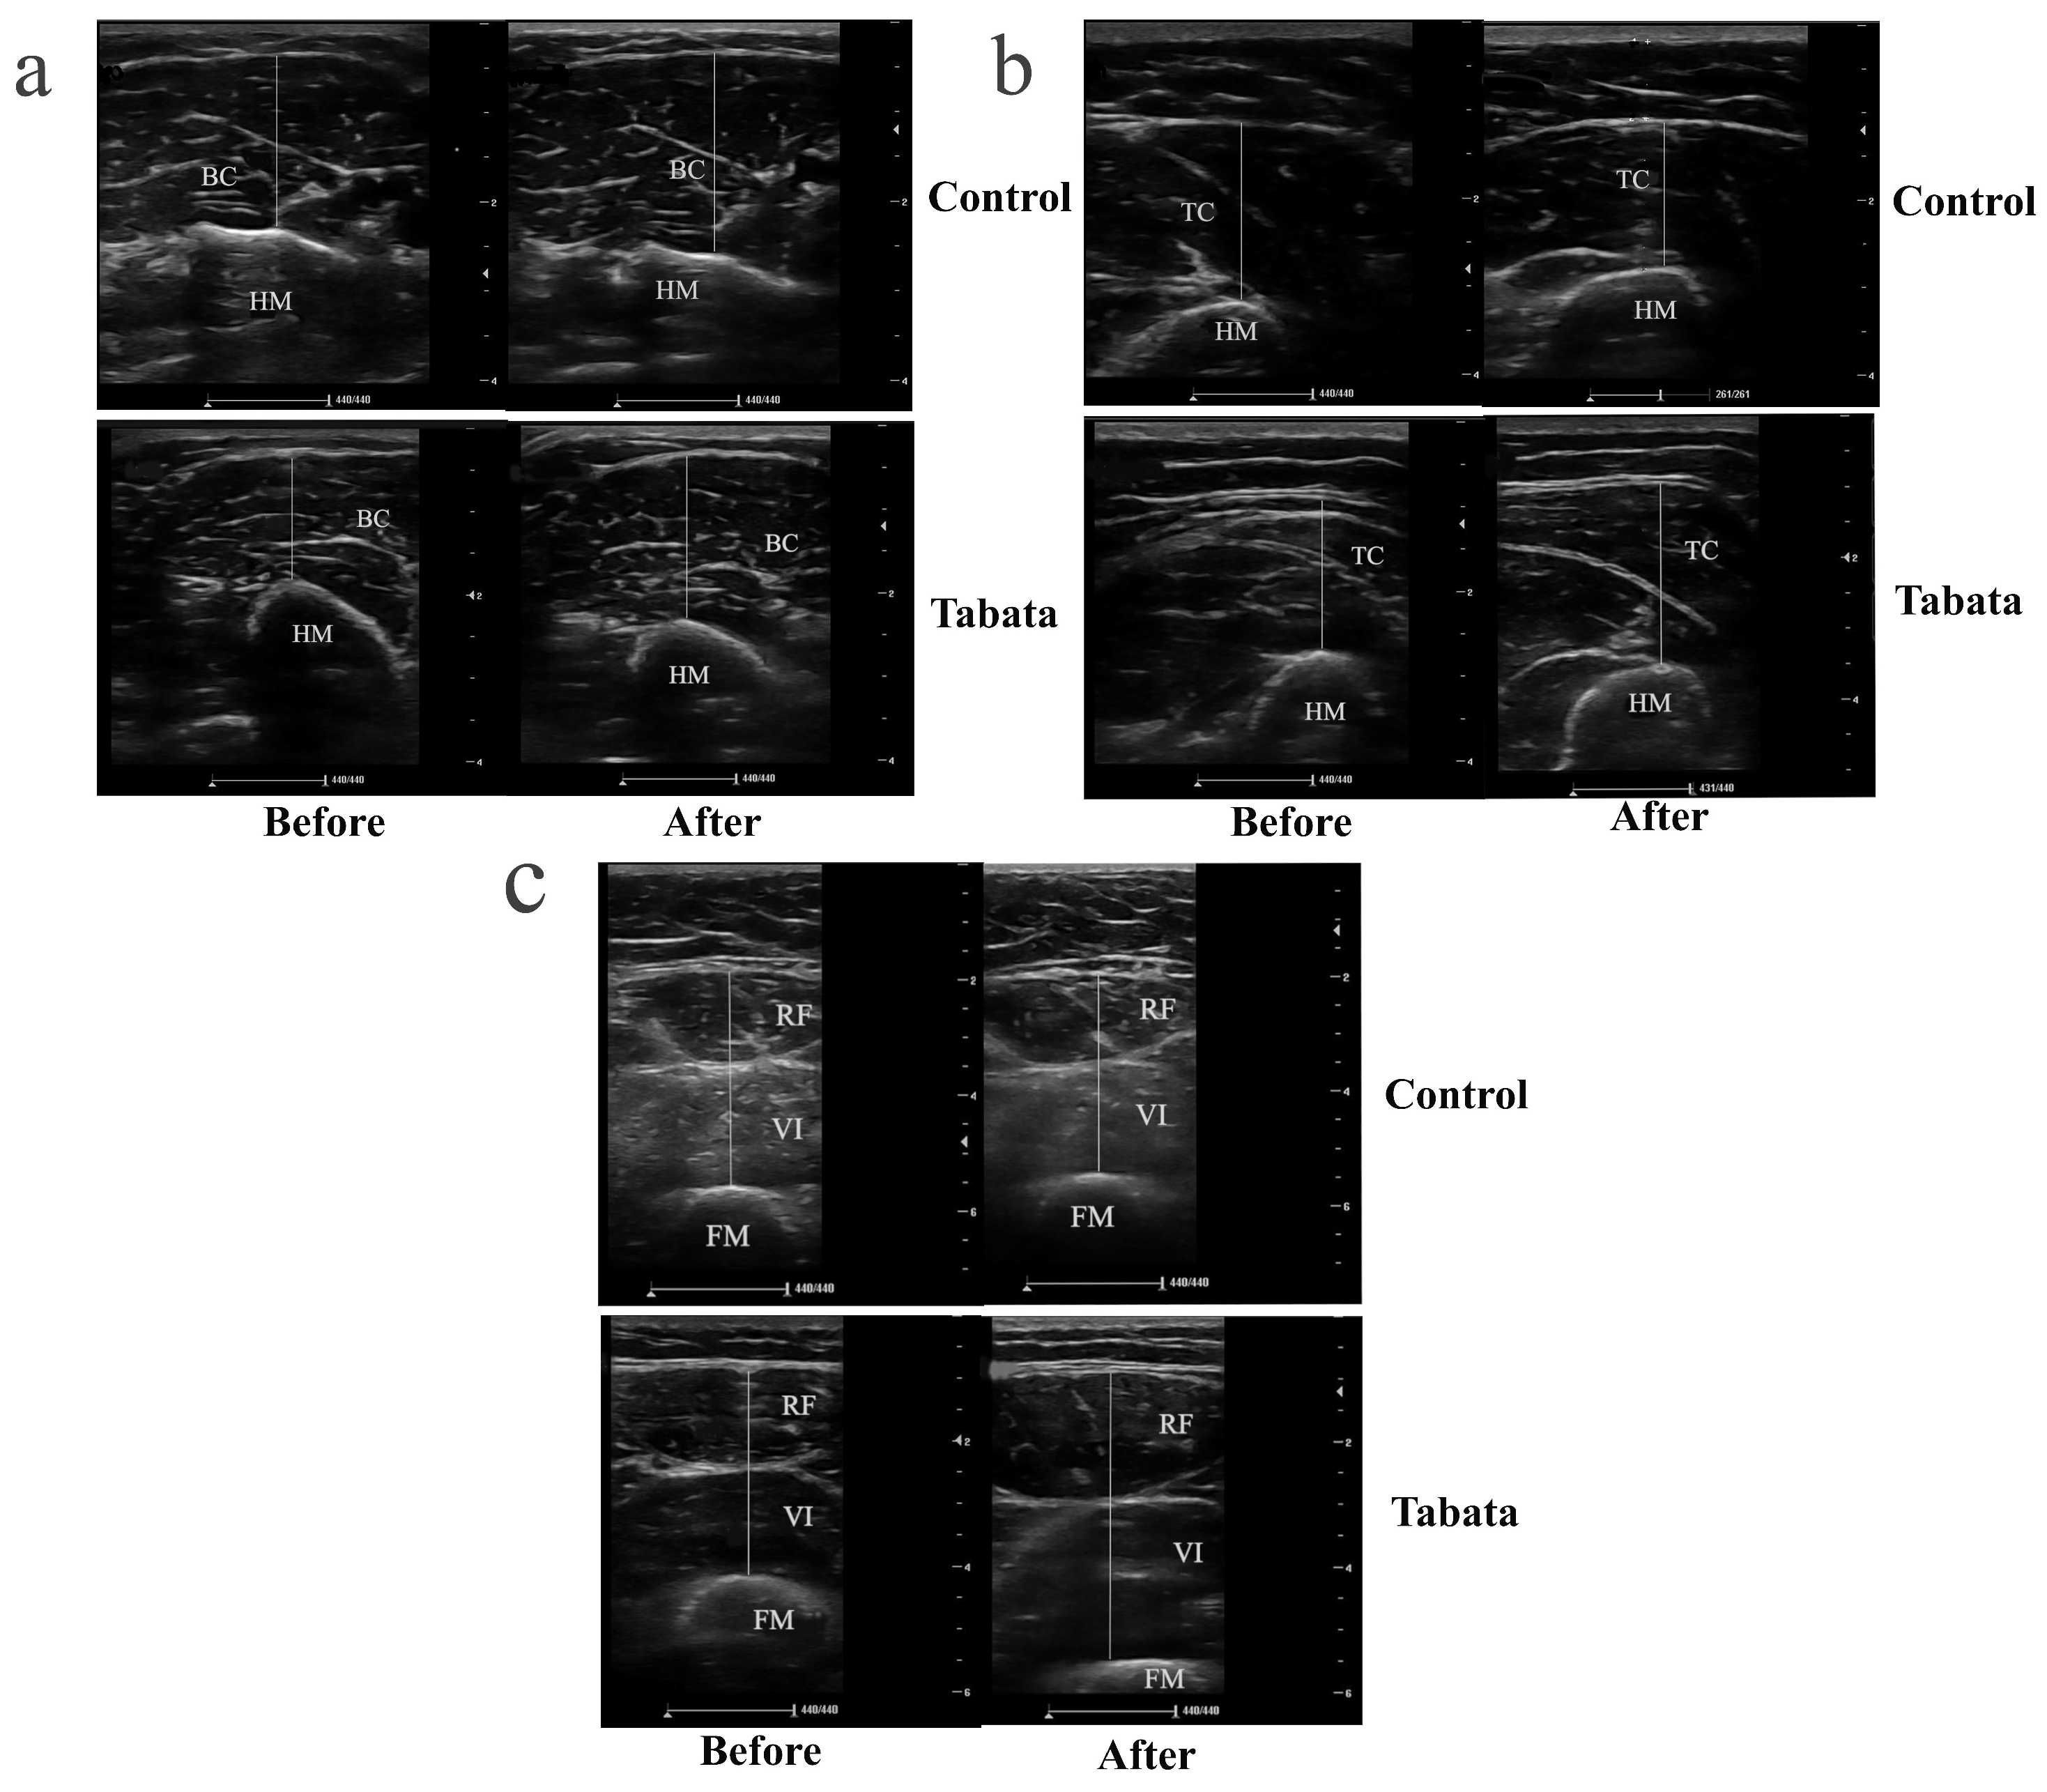

The Tabata group showed significant increases in muscle thicknesses of 0.30 ± 0.08 cm (biceps), 0.78 ± 0.25 cm (triceps), 0.35 ± 0.10 cm (rectus femoris), and 0.85 ± 0.34 cm (vastus intermedius) compared to both the pre-test period (all p < 0.05) and the control group (p = 0.001, ES = 0.26; p = 0.028, ES = 0.90; p = 0.003, ES = 0.84; p = 0.004, ES = 0.88, respectively), as shown in Figure 3 and Figure 4.

Figure 4.

Ultrasound images demonstrating muscle thickness of participants in control and Tabata groups before and after 12-week intervention. (a) Transverse scan of biceps muscle (BB), with the hyperechoic, curvilinear structure in the lower part of the image representing the humerus (HM). (b) Transverse scan of triceps muscle (TC), where the hyperechoic, curvilinear structure in the lower part of the image corresponds to the HM. (c) Transverse scan of quadriceps muscle, comprising rectus femoris (RF) and vastus intermedius (VI); the hyperechoic, curvilinear structure in the lower part of the image represents the femur (FM). Solid straight lines indicate the method used to measure the thickness of each muscle.